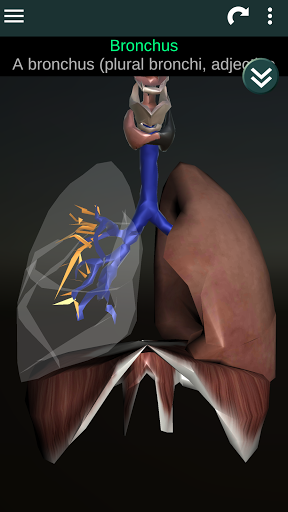

(الأجهزة الداخلية في)

Internal Organs 3D Anatomy 3.4

يمكنك هنا تنزيل ملف حزمة تطبيق أندرويد "Internal Organs 3D Anatomy" الخاصة بجهازVodafone Smart N9 Lite مجانًا، نسخة ملف حزمة تطبيق أندرويد - 3.4 للتحميل على Vodafone Smart N9 Lite اضغط ببساطة على هذا الزر. إنه سهل وآمن. نحن نقدم فقط ملفات حزمة تطبيق أندرويد الأصلية. إذا انتهكت أية مواد موجودة في الموقع حقوقك قم بإبلاغنا من خلال